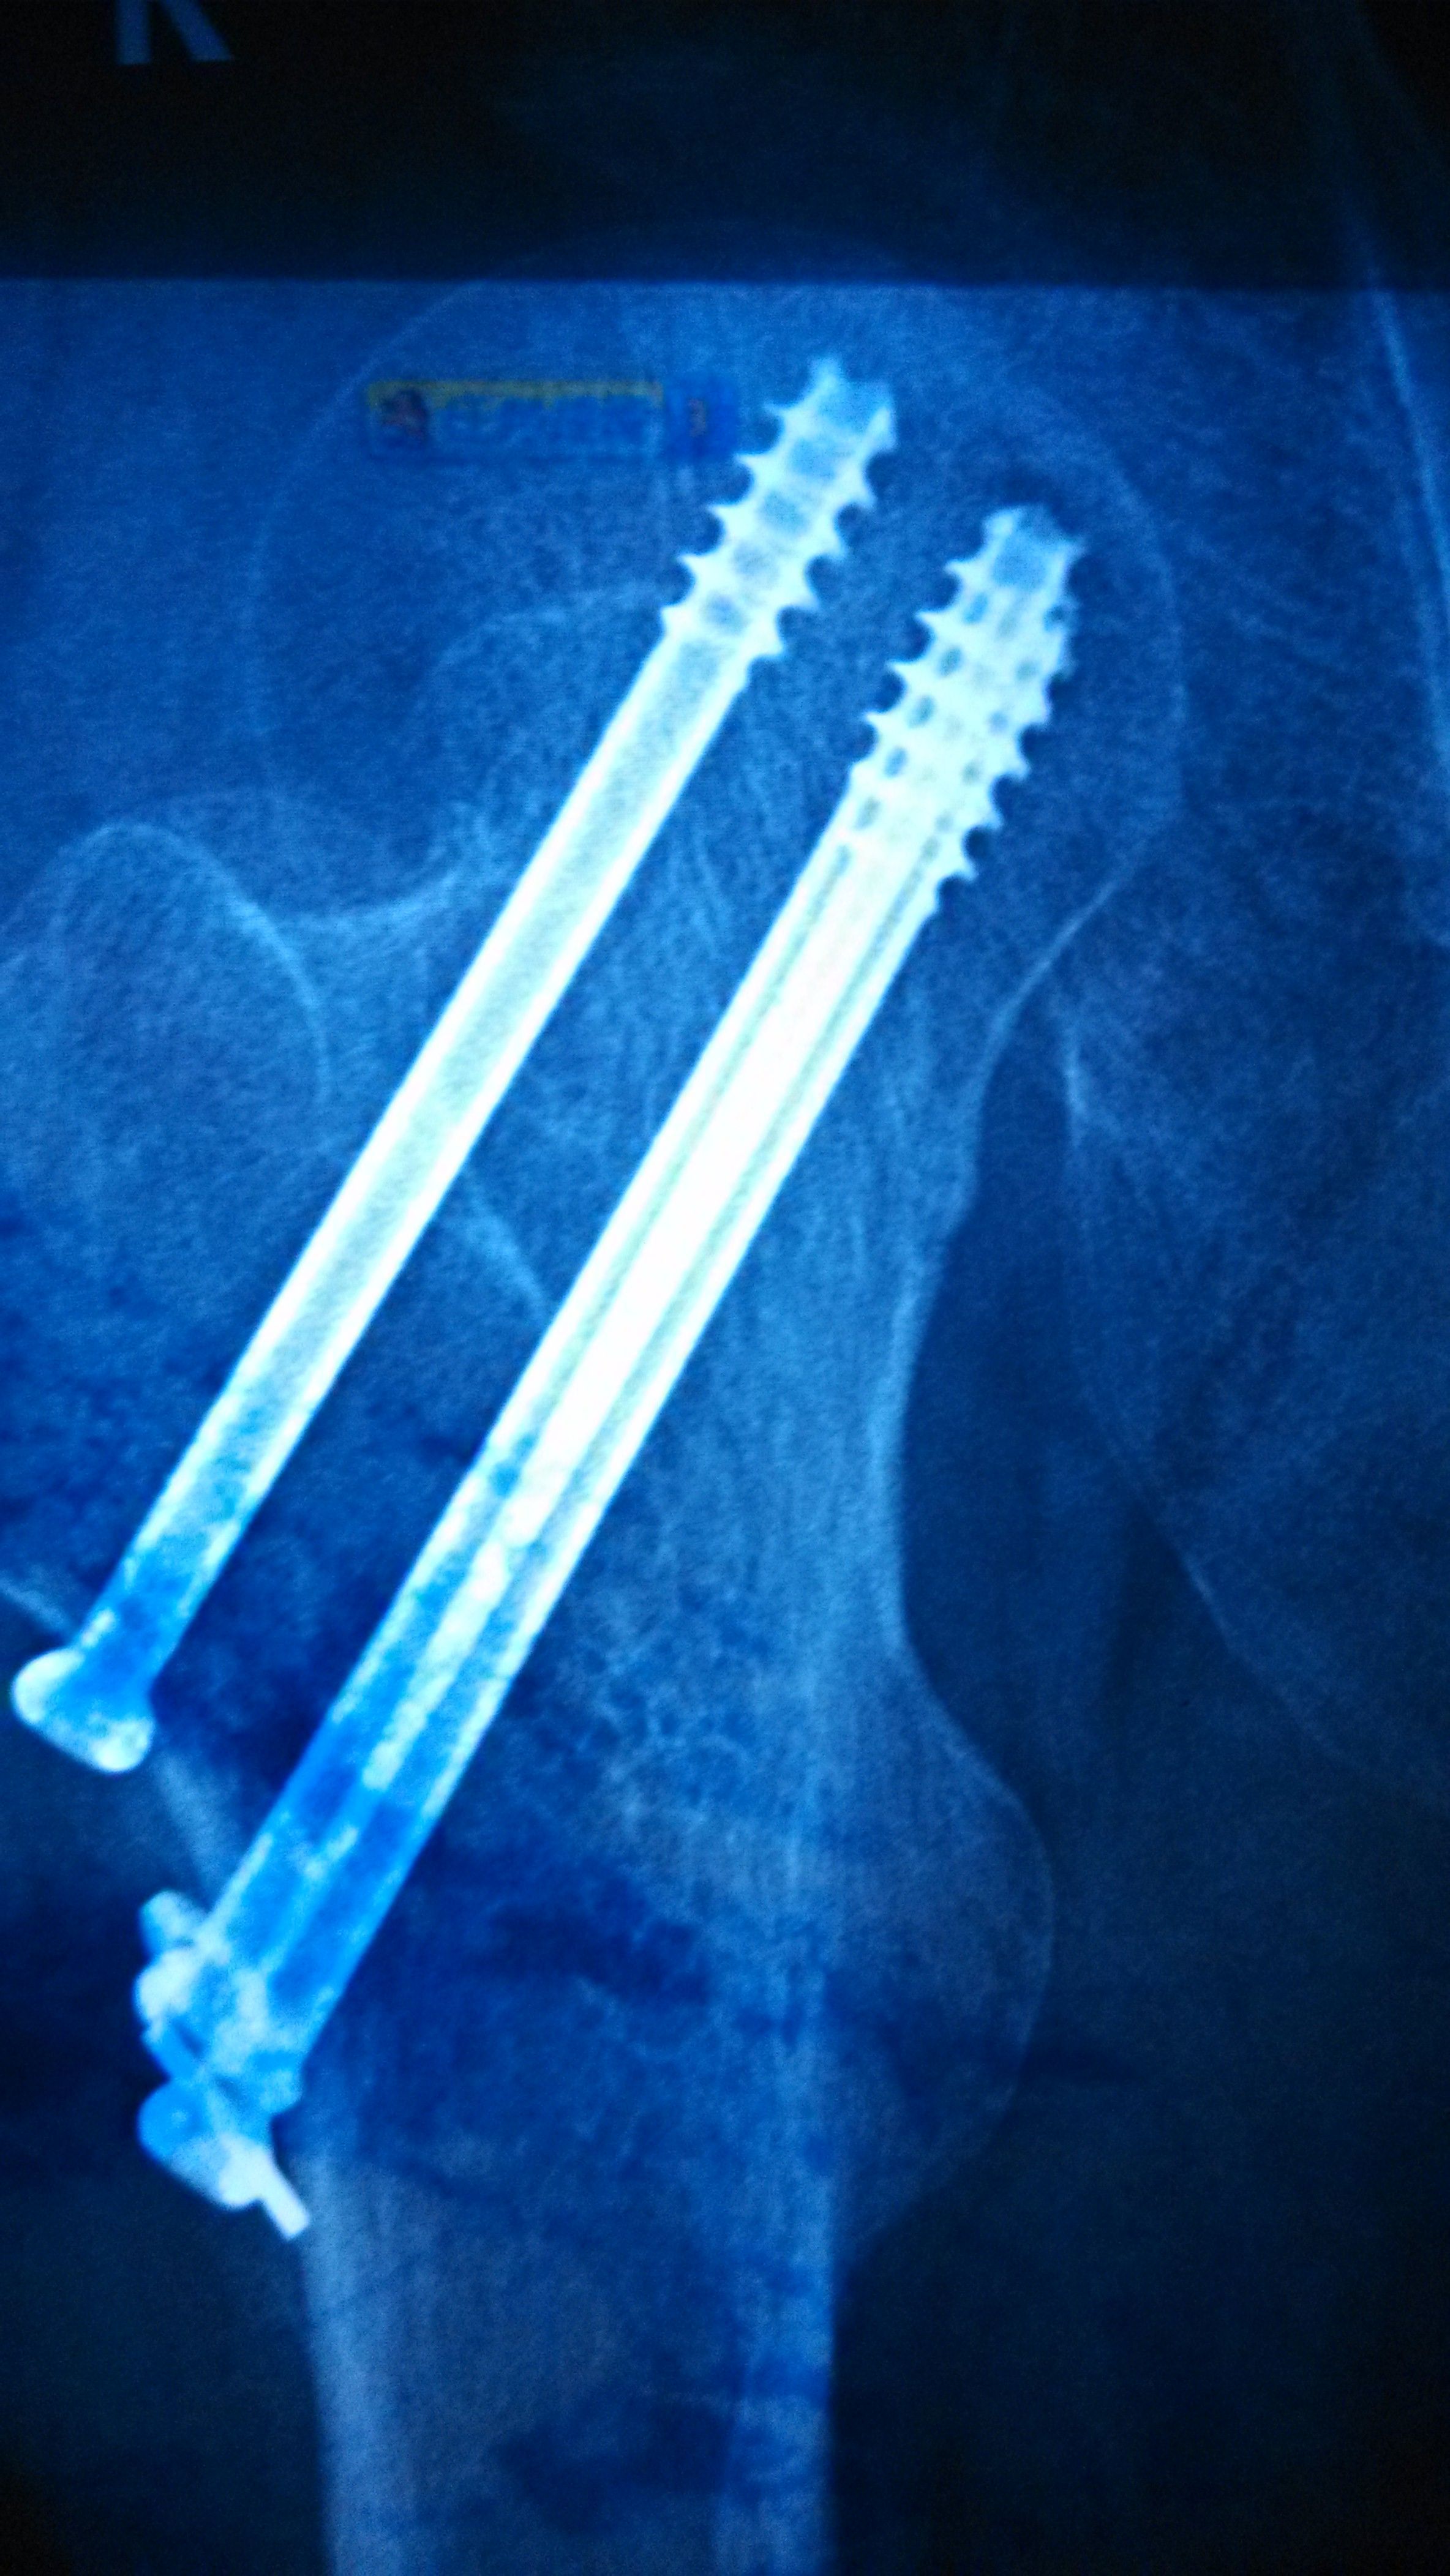

股骨颈骨折内固定七个月了,麻烦教授给看看~能不能够骑单车锻炼,谢谢了 点击展开 匿名用户 2015-06-03 21:00 满意回答 你好,股骨颈骨折内固定七个月了洞炼舞,看片队垃上,愈合不错,可糟相以锻炼的。 2015-06-03 21:08 宝宝知道提示您:回答为网友贡献,仅供参考。 相关问题 刚生完宝宝2个月这样能不能骑单车锻炼呐? 我怀孕三四周了,我每天都坚持去健身房跑步,骑单车,每次都要锻炼至少一个小时 吃饭也不忌口 股骨颈骨折七个月,现在医生诊断有坏死可能,请咨询如何进行康复治疗